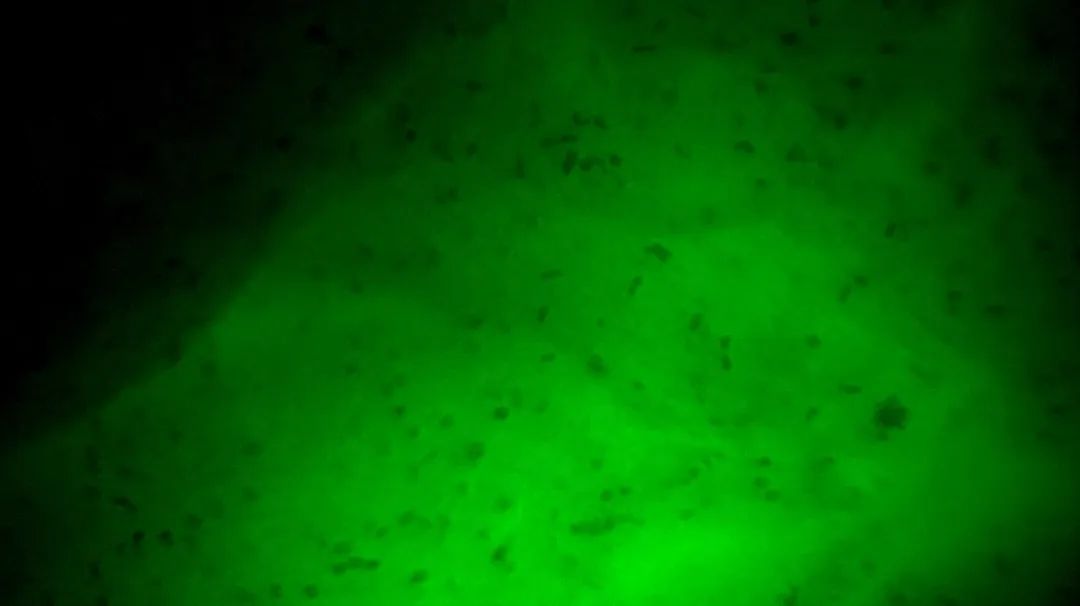

3次切緣掃查的EndoSCell?細(xì)胞圖像

2

陽性,細(xì)胞核異型、密集、分布不均勻